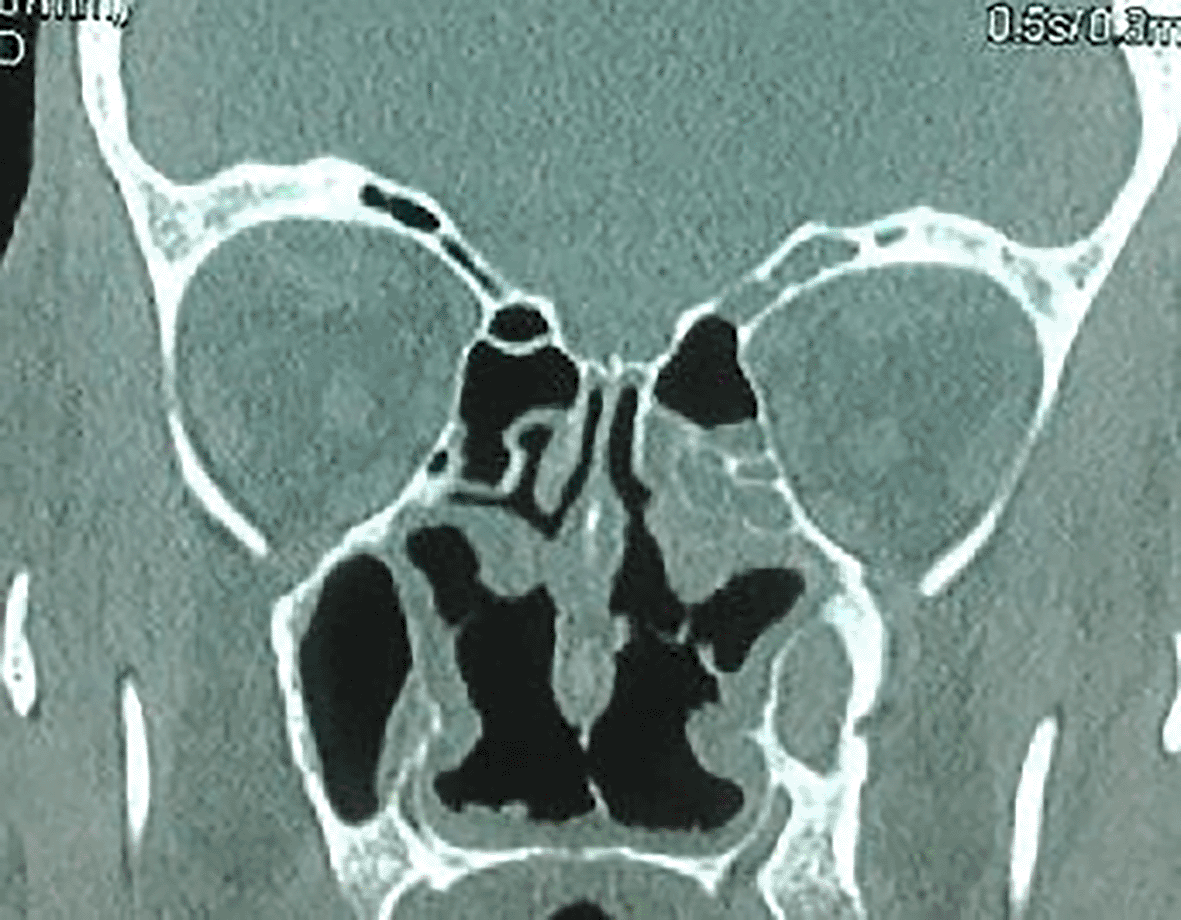

The craniofacial and the thoracoabdominal computed tomography (CT) scans showed ethmoid and maxillary sinusitis, low facial bone density (Figure 2), multiple mediastinal and hilar lymphadenopathy, diffuse small pulmonary nodules, and hepatomegaly. The clinical, biological, radiological, and histological findings substantiated the diagnosis of GPA.

2f1fdcf8-5f73-4cc4-a14f-30b48de9e110_figure2.gif

Figure 2. Ethmoid and maxillary sinusitis and low facial bone density.